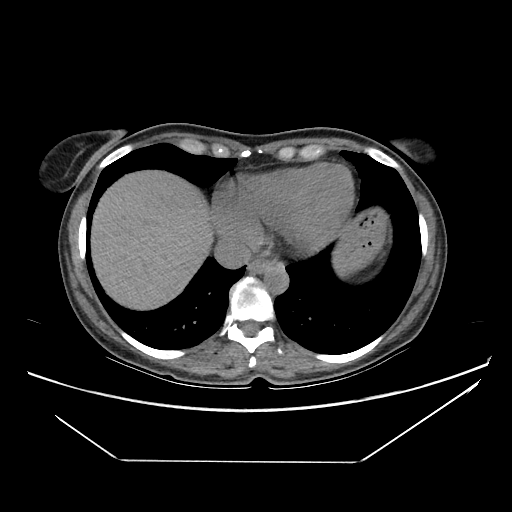

Slice 70 Targeting Evaluation

Slice: Slice_70

Conversion: NATIVE β†’ VENOUS

Targeted Slice 70 - Mediastinum Window Analysis (Generated vs Real Venous)

0.698

Mediastinum SSIM

82.1

Mediastinum RMSE

35.5

Mediastinum MAE

Image Grid

4Γ—3 grid: Rows show different image types (Original NATIVE, Reconstructed NATIVE, Original VENOUS, Generated VENOUS), Columns show windowing techniques (No Window, Lung Window, Mediastinum Window)

Mediastinum window (WL 40, WW 400 β†’ Low βˆ’160, High +240)